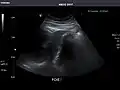

Kidneys: Right and left kidneys measure 11.5 cm and 12 cm in length respectively. No hydronephrosis. Small left lower pole kidney cyst.

Right kidney -